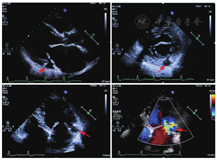

患者女性,53岁,因"反复胸闷,活动后气促"就诊,查体:呼吸20次/min,脉搏104次/min,血压121/89 mmHg。心界向左扩大,心率110次/min,心房颤动节律,心尖可闻及3/6级收缩期吹风样杂音。既往有高血压病史,规律服用贝那普利10 mg/d,血压控制不佳。心电图提示:持续性心房颤动(图1)。经胸壁超声心动图(TEE)提示:(1)二尖瓣重度关闭不全致左房、左室增大;(2)左室憩室形成(二尖瓣后瓣环)(图2)。心脏CT提示:(1)左心增大,二尖瓣后叶根部-左心室后下壁膨出瘤(真性)可能;(2)前降支(LAD)近端轻度狭窄约20%,第二对角支(D2)起始处中度狭窄约60%(图3)。为排外冠状动脉病变行冠状动脉造影检查,结果提示:右冠优势(+),左主干(LM)、LAD、回旋支(LCX)、右冠状动脉(RCA)未见明显狭窄(图4)。

可见左室舒张末内径61 mm,左房收缩末内径52 mm,左室射血分数60%,二尖瓣口大量偏心反流。二尖瓣后瓣环处类圆形无回声结构(箭头所示),大小约20 mm×18 mm,开口于左室,无血栓附着,收缩正常,没有矛盾运动。其内有血流通过,经过开口时可见血流加速信号